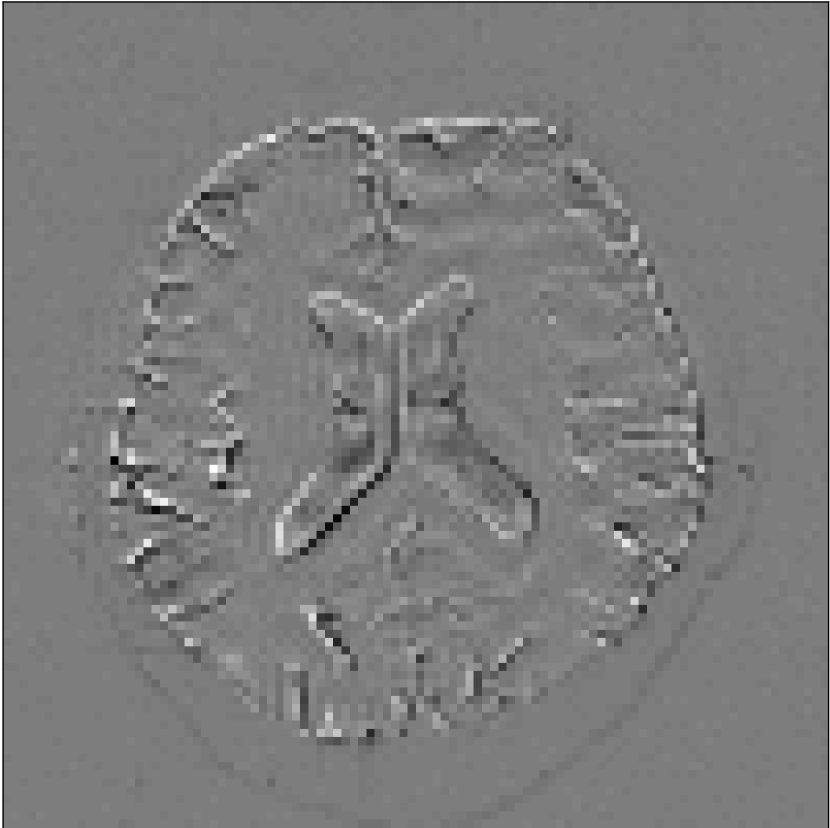

We also examined the CCNN activations (i.e., images from each channel after a CNN layer) in the case of the edge phantom, which are shown in Figure 5.

Input, 𝐱tsubscript𝐱𝑡\mathbf{x}_{t}

Refer to caption

Activations

No PF

7/8 PF

6/8 PF

5/8 PF

Figure 5: Activations across PF factors. (top) Original 𝐱tsubscript𝐱𝑡\mathbf{x}_{t} input to the neural network at an SNR of 1024. (bottom) Activations from one channel prior to first wavelet transform. The activations in early layers enhance the Gibbs artifact, which is then subtracted from the image in the final step.

Figure 5 shows one channel (out of 64) from the activations after three convolutional steps and prior to the first wavelet transform. In early layers, we found that the networks tended to enhance Gibbs artifacts for removal in the final layers. Other features of the image are detected in the other network channels, as shown in Figure 1 of the supplementary material. Some channels detect changes in the phase of the image, while other channels detect flat regions. The overall properties of the network depend on integrations of all of these channels. We also examined activations in other layers after wavelet downsampling operations, but the activations in these layers were less interpretable.